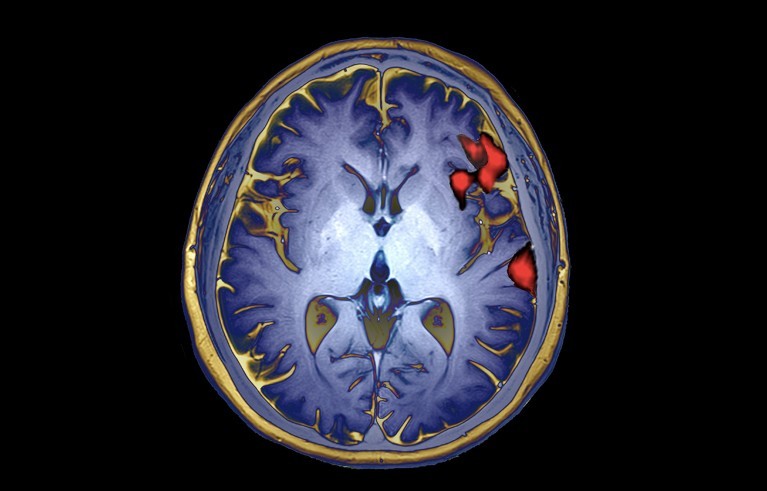

医学成像显示语音产生过程中的大脑活动(人工着色)。

图片来源:《自然》网站